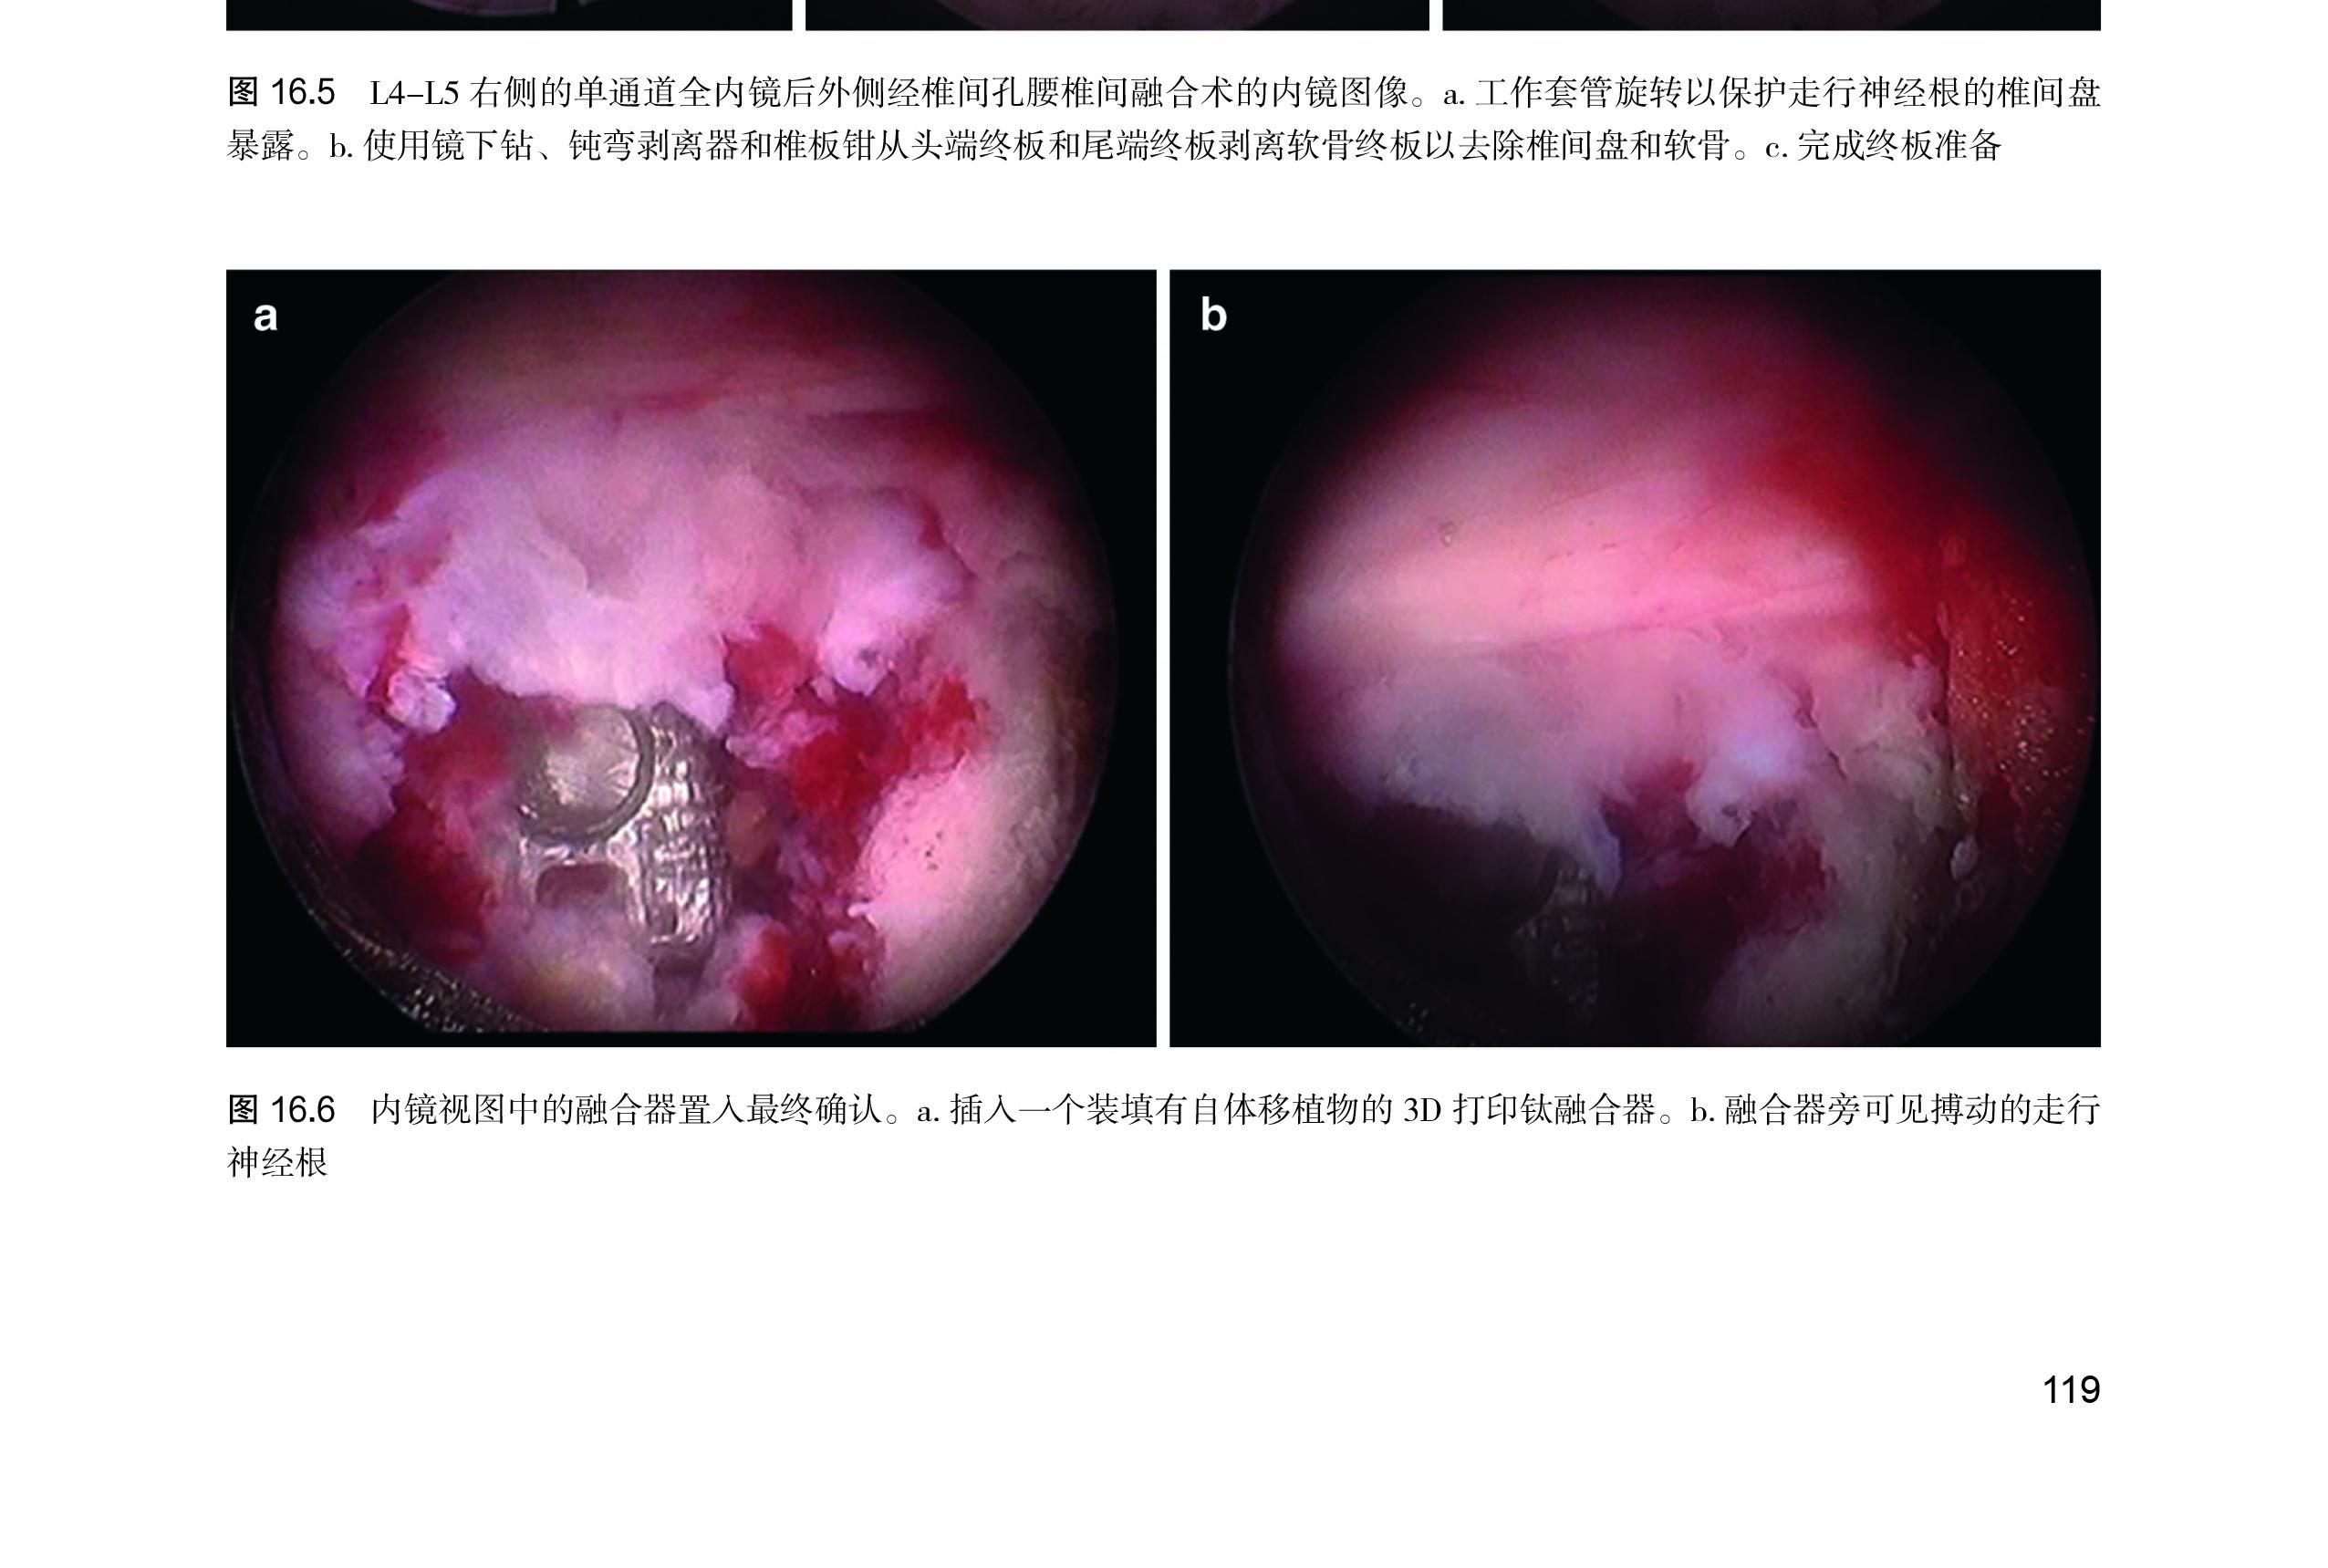

第 16 章 单通道全内镜后外侧经椎间孔腰椎间

融合术 ……………………………… 116